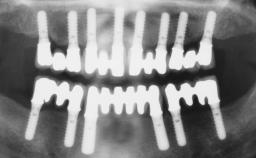

Immediate Loading of Four Implants in the Mandible and Six Implants in the Maxilla and Final Restoration with a Full-Arch Metal Framework FDP and a Full-Arch CAD/CAM Zirconia Framework FDP

# of Implants 10

Bone Augmentation Horizontal|Simultaneous

Loading Protocol Immediate